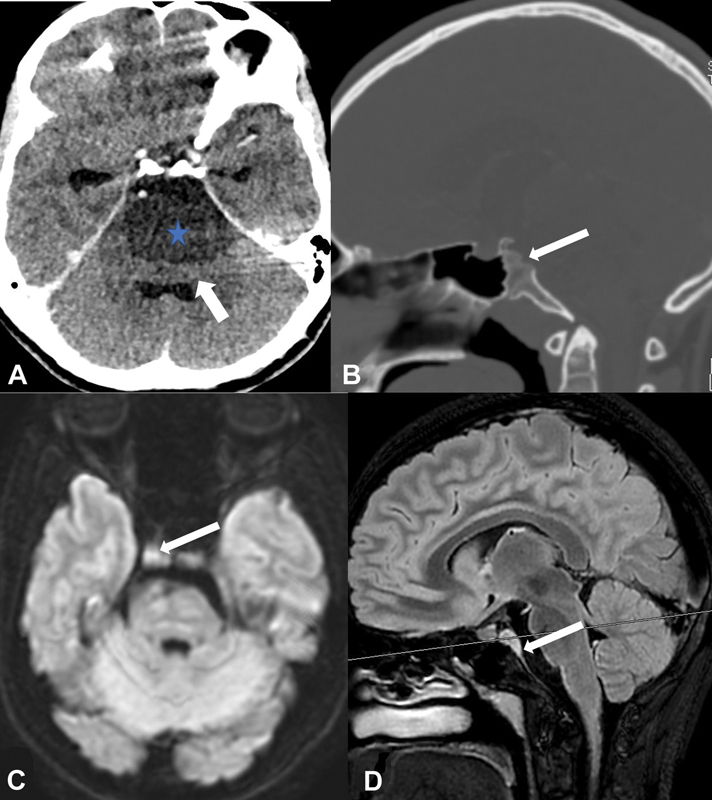

硬膜前脊索瘤是一种极为罕见的肿瘤,与骨内源性脊索瘤相比,它具有良性特征,不会复发,预后良好。放射学上,它可能与表皮样囊肿相似,给影像学带来挑战。在此,我们介绍一例因头痛、肢体和面部无力而就诊的中青春期女孩的病例。在大脑前蝶窦发现了一个不强化、弥散受限、以硬脑膜内囊性包块为主的肿块病变。起初怀疑是表皮样囊肿,但组织病理学检查发现是脊索瘤。蝶窦的破坏很重要,脊索瘤应纳入鉴别诊断。

Intradural prepontine chordoma is an extremely rare entity and depicts benign features with no recurrence and has a good prognosis as compared with bone endogenous chordoma. Radiologically, it may mimic an epidermoid cyst and present an imaging challenge. Here we present a case of a middle adolescent girl who presented with headache along with limb and facial weakness. A nonenhancing, diffusion-restricting, predominantly intradural cystic-appearing mass lesion was seen in the prepontine cistern. Initially, an epidermoid cyst was suspected, but histopathology revealed it to be a chordoma. Destruction of the clivus is important and chordoma should be included in differential diagnosis.